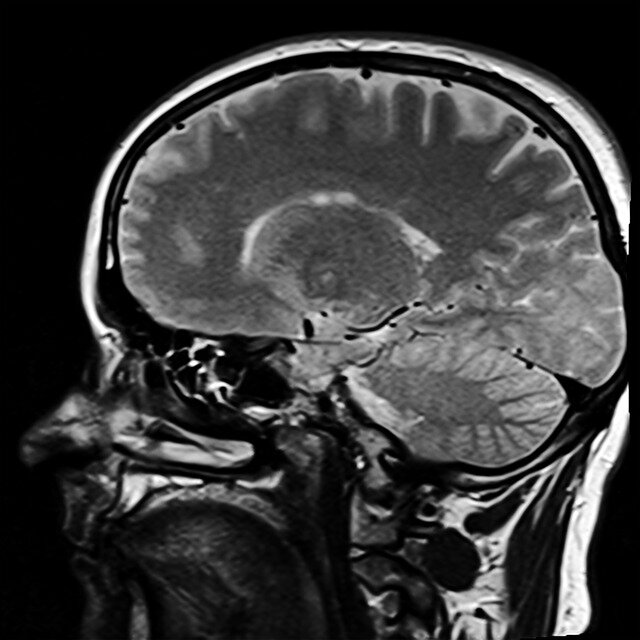

Другой метод, магнитно-резонансная томография, основан на явлении ядерного магнитного резонанса. Это сложный феномен, так что его картину придётся несколько упростить для лучшего понимания.

Ядра атомов некоторых элементов, например водорода, взаимодействуют со сторонним сильным магнитным полем. Сами эти ядра имеют электрический заряд. А электричество и магнетизм всегда связаны, при этом одно порождает другое. Так что ядра атомов водорода фактически являются микроскопическими магнитиками. Говорят, что они обладают магнитным моментом - величиной, характеризующей наличие соответствующего поля у частицы.

Ядра водорода во внешнем магнитном поле способны изменять направление собственного магнитного момента а затем возвращаться в исходное состояние* (в физике этому процессу даже название придумали - релаксация). При этом выделяется энергия, регистрируемая аппаратурой. Так и работает МРТ.

Атомы водорода входят в состав воды, которой много в наших органах, поэтому магнитно-резонансную томографию применяют в том числе для изучения мозга и поиска опухолей. Кстати, до 1987 года метод назывался ядерно-магнитно-резонансной томографией, но затем из-за нарастающей в обществе боязни радиации, термин решили несколько скорректировать. Даже не смотря на то, что в процессе исследования не применяются рентгеновские и гамма-лучи.